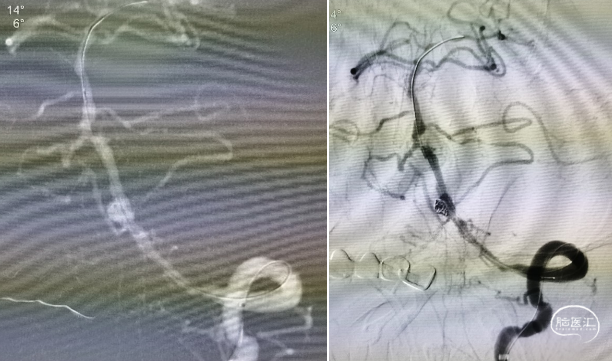

Transcend携带SL-10微导丝进入左侧大脑后动脉,明确真腔内后交换Gateway2.0mm×15mm以命名压缓慢进行两次扩张,造影见现在较前改善,动脉瘤近端存在狭窄暂时未扩张

首先尝试并行式支架释放,但ProwlerPlus通过后SL-10无法进入动脉瘤内,考虑动脉瘤近端狭窄较重,考虑患者血管情况较差,未尝试强行通过,遂考虑穿支架网眼。尽管选择的是4.5 mm×37 mm的EP支架,但长度仍然捉襟见肘,头端尝试释放于基底动脉时末端距离不足,考虑椎基底交界处血管扩张情况尚满意,遂将支架释放于椎动脉